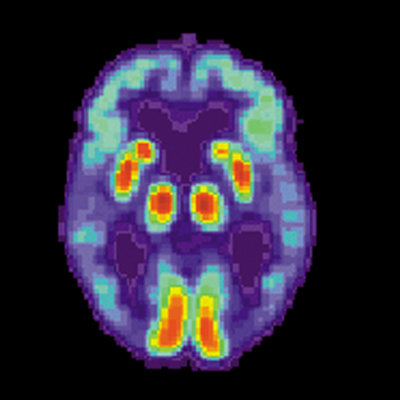

According to the National Institute on Aging, experts estimate that more than five million people in the United States have Alzheimer's disease, a condition that damages memory and cognitive function. Dr. David Holtzman - Professor and Chairman of the neurology department at the Washington University School of Medicine and associate director of the Charles F. and Joanne Knight Alzheimer's Disease Research Center - explains what is happening in the brain of someone with Alzheimer's. He also describes his own laboratory's research into the disease and shares why he believes that it should be treatable.